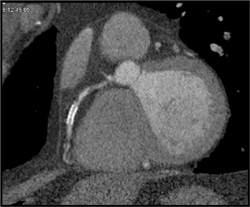

Dense Myocardium Die to Renal Failure